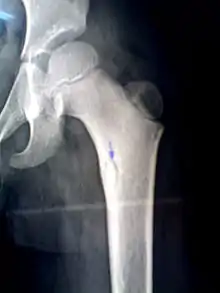

Sequestrum

A sequestrum (plural: sequestra) is a piece of dead bone[1] that has become separated during the process of necrosis from normal or sound bone.

It is a complication (sequela) of osteomyelitis. The pathological process is as follows: